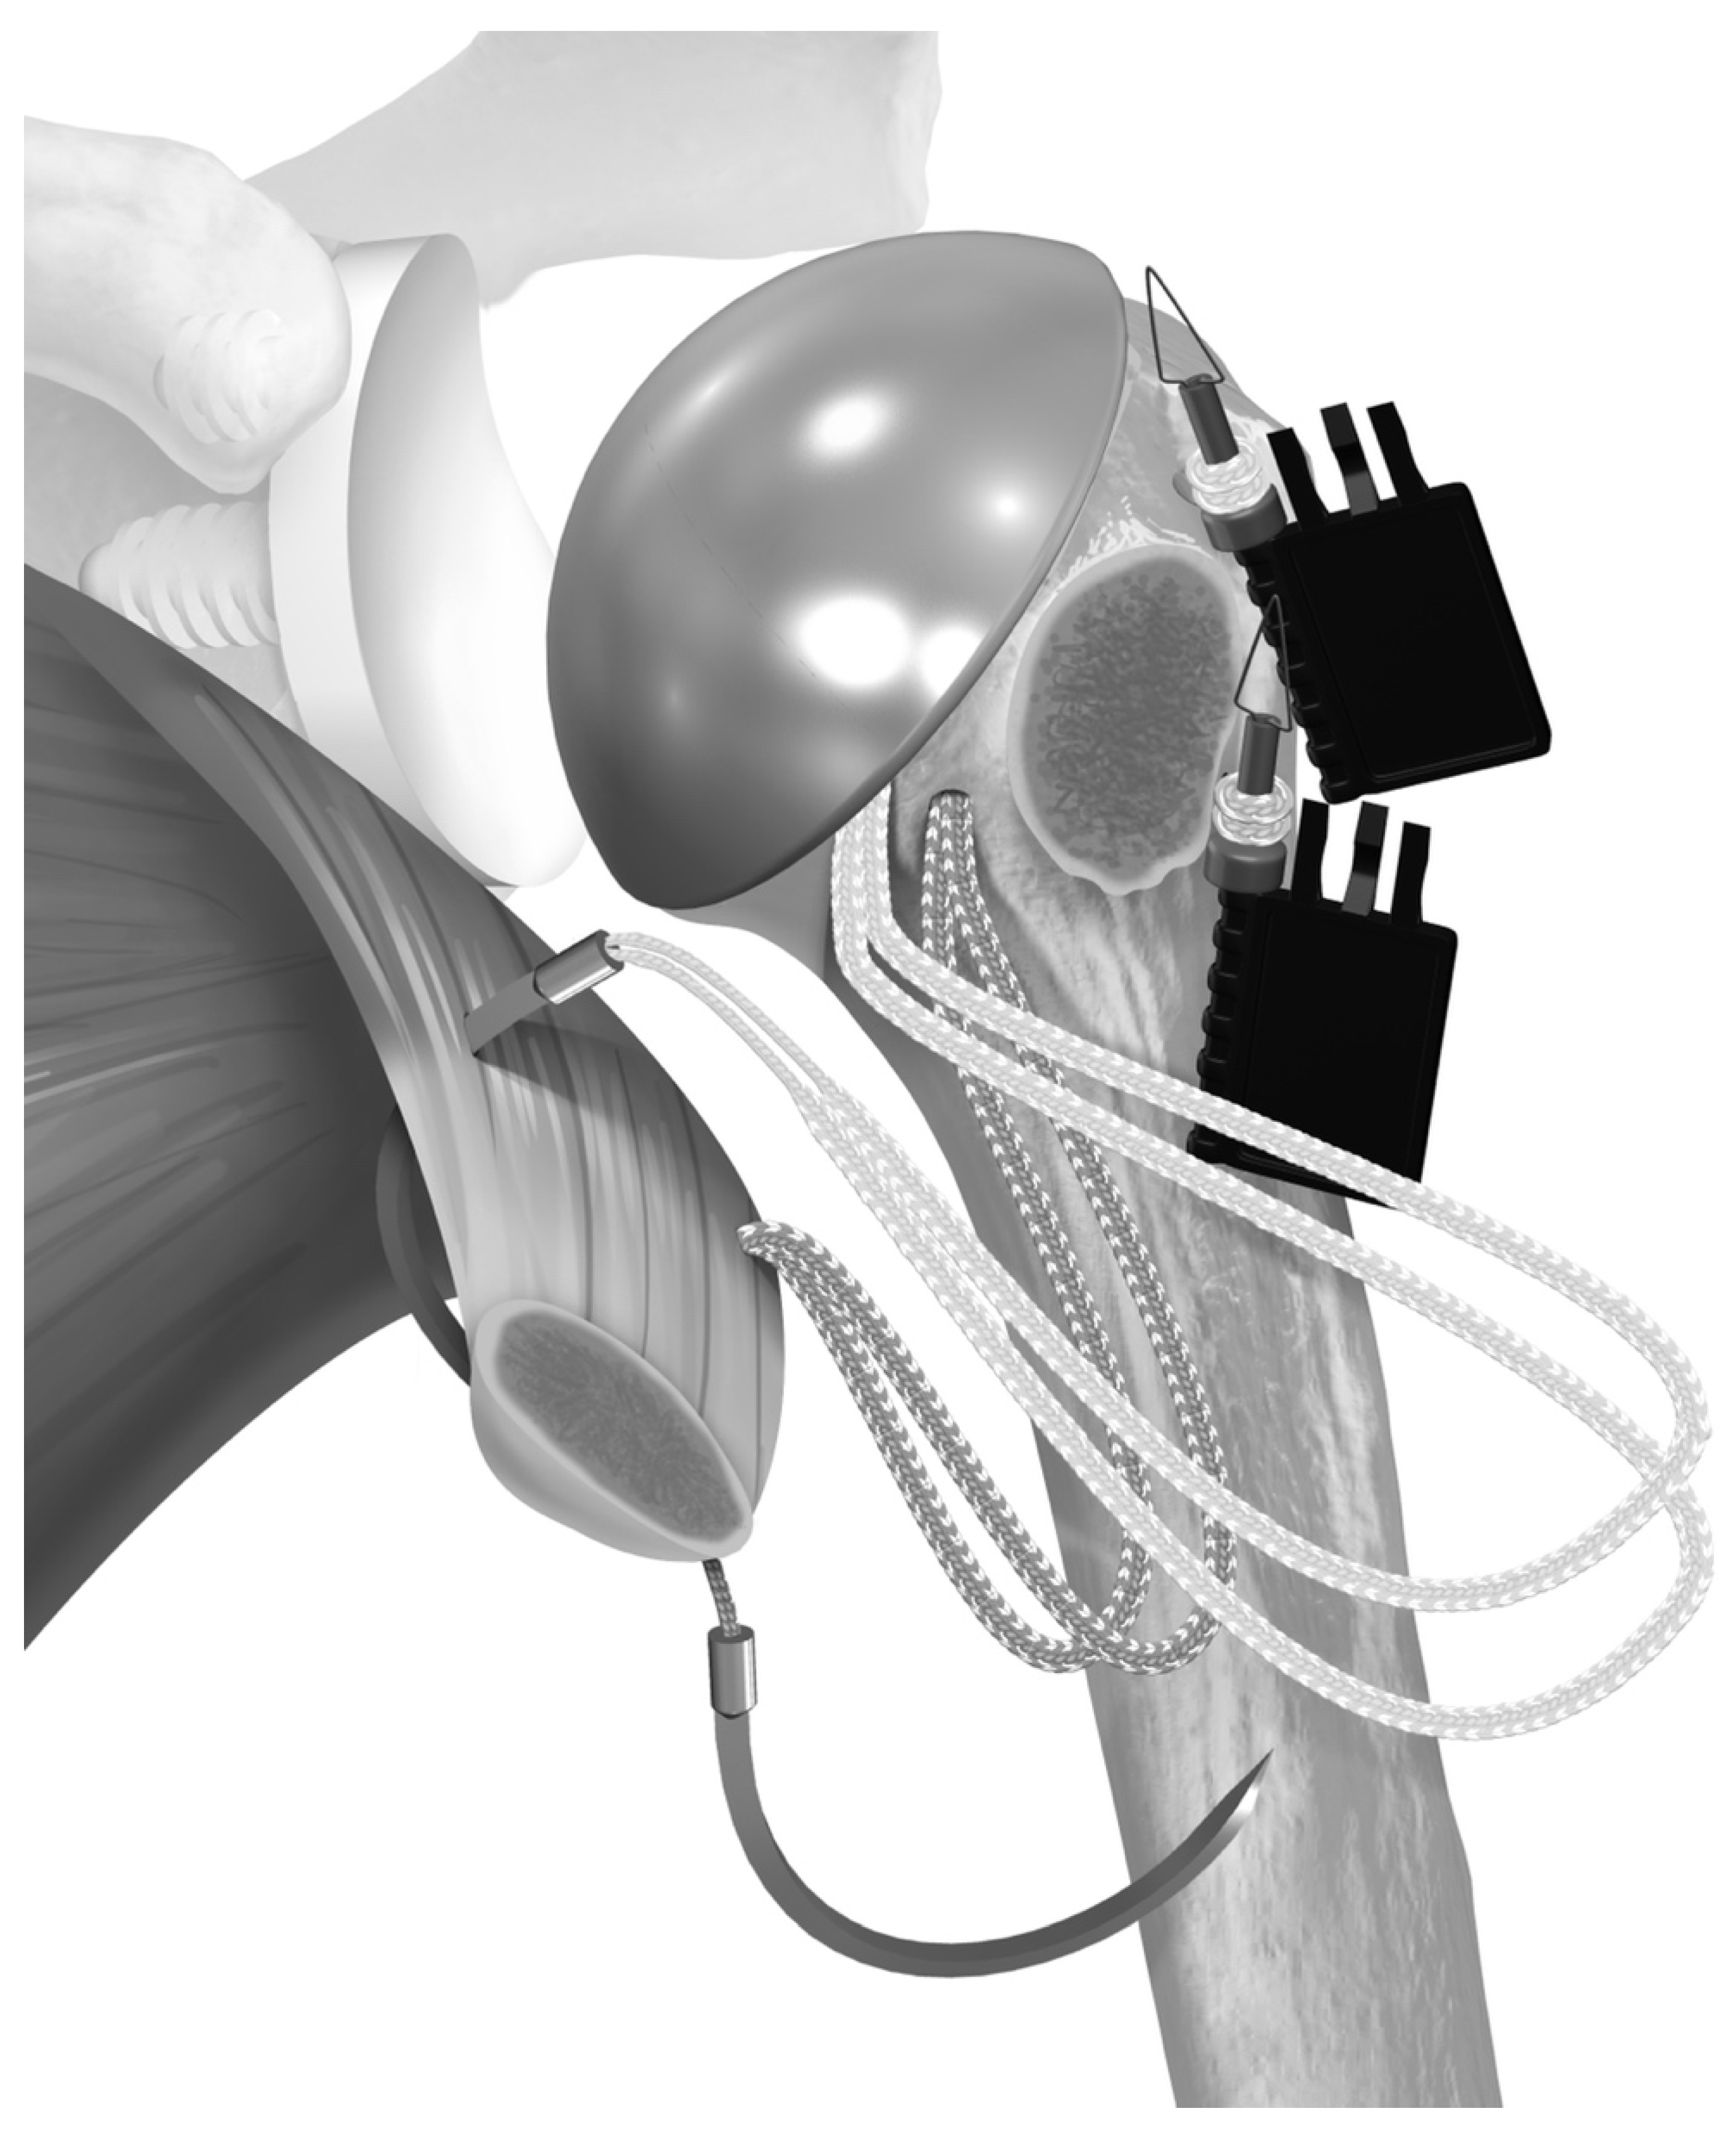

2.2. Surgical Technique

- Denard, P.J.; Noyes, M.P.; Lädermann, A. A Tensionable Method for Subscapularis Repair after Shoulder Arthroplasty. JSES Open Access 2018, 2, 205–210. [Google Scholar] [CrossRef]

- Heckman, D.S.; Hoover, S.A.; Weinhold, P.S.; Spang, J.T.; Creighton, R.A. Repair of Lesser Tuberosity Osteotomy for Shoulder Arthroplasty: Biomechanical Evaluation of the Backpack and Dual Row Techniques. J. Shoulder Elb. Surg. 2011, 20, 491–496. [Google Scholar] [CrossRef]

- Lederman, E.; Streit, J.; Idoine, J.; Shishani, Y.; Gobezie, R. Biomechanical Study of a Subscapularis Repair Technique for Total Shoulder Arthroplasty. Orthopedics 2016, 39, e937–e943. [Google Scholar] [CrossRef]